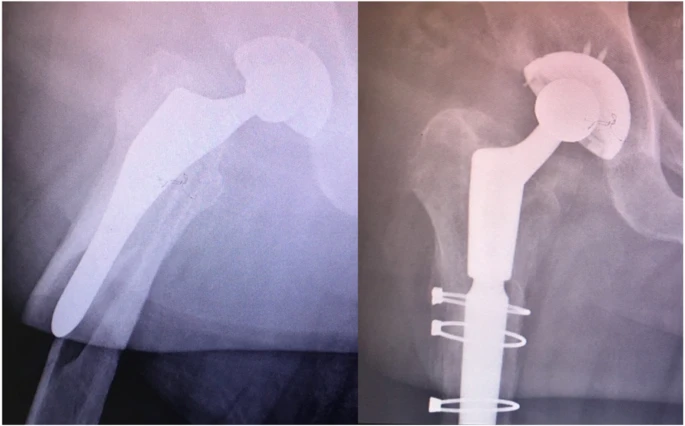

Bien que le but de cette étude n'ait pas été d'étudier les résultats du traitement, dans cette étude, les fractures flip-flop inversées ont généralement été révisées avec une arthroplastie de la tige portante distale et la fixation des fragments proximaux de la fracture avec des fils ou des plaques de cerclage.

Un exemple d'un patient traité avec cette approche est montré, montrant la réalisation de la guérison (Figure 3).

Figure 2 Modèle de fracture inversée du flip-top.

Figure 3 Arthroplastie et fixation du fil de cerclage pour les fractures du lambeau rétrograde.